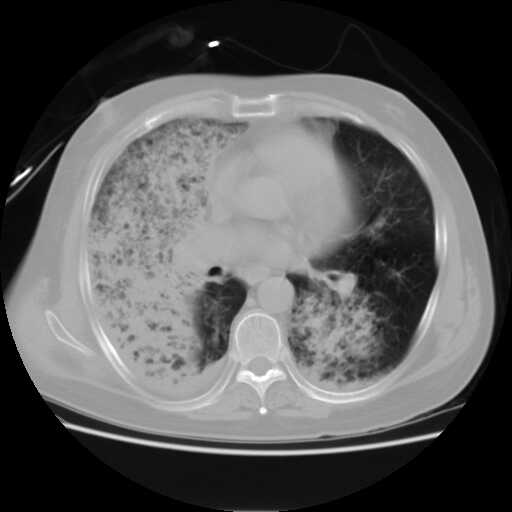

患者,男,60岁,病史如下:

2008.8.11胸片

病变从8.11-8.17明显改变,增多,以蜂窝状改变为主,类蜂窝肺,似弥漫性肺泡癌,但是病变进展太快,不符合弥漫性细支气管肺泡癌。因此考虑为特殊微生物感染,多以霉菌类常见,建议细菌微生物学检查。

结合临床慢支炎肺气肿,肺心病病史,三次胸片观察可见病情发展变化迅速,病情凶险,考虑多重感染伴ards.